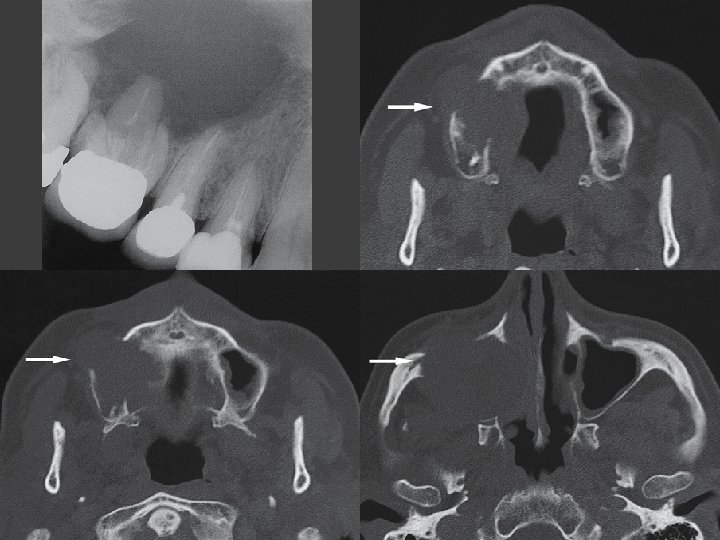

Coronal CT image Coronal T 2 - fat suppressed MRI Squamous cell carcinoma, maxilla; 70 -year-old female with some bleeding from tender soft tissue mass of right gingival mucosa.